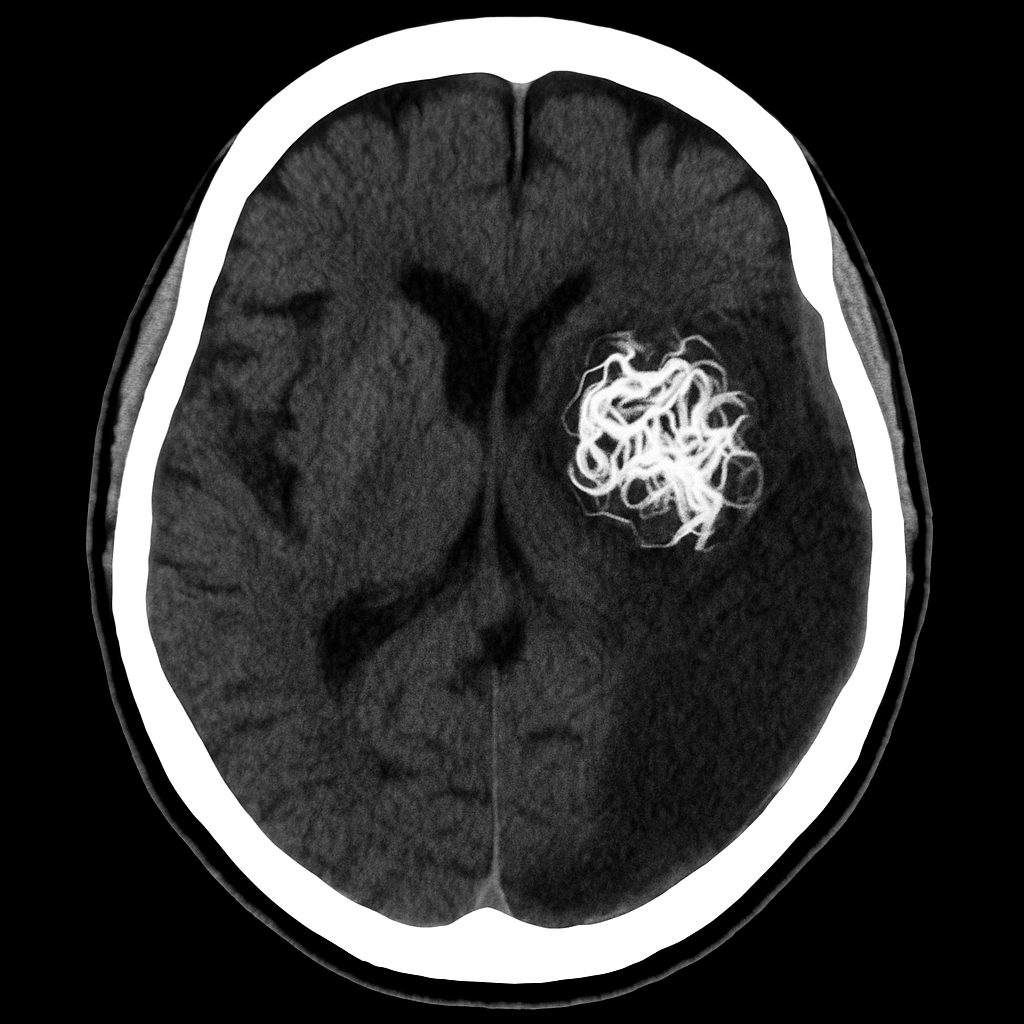

Normally, your blood vessels work like a well-planned road system. Arteries carry blood away from your heart, veins bring it back, and capillaries in the middle help everything slow down and transition smoothly. But with an AVM, those capillaries are skipped entirely. Instead, arteries and veins are tangled together like a bunch of knotted earphones, pushing blood through at the wrong pressure and speed.

So if you’re wondering what AVM is in plain terms: it’s a hidden tangle of blood vessels in your body’s wiring that you’re likely born with—and when it breaks, everything changes.

That’s when my neurosurgeon explained it. I had something called an arteriovenous malformation. A rare tangle of blood vessels in my brain. It had been there since birth—a congenital condition. I didn’t cause it. I couldn’t have prevented it. I just had it, silently, all that time.